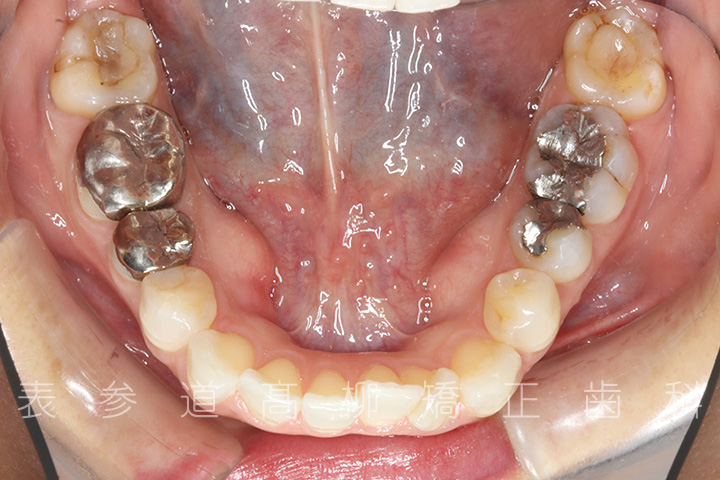

上下4本第二小臼歯抜歯症例

口呼吸と舌癖で前歯が咬み合わない患者様の症例をご紹介いたします。

治療経過

術前術後の比較